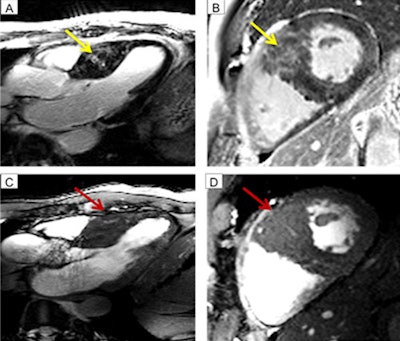

Images show fibrosis at 3-tesla MRI (top row, yellow arrow) with a long-axis view (A) and short-axis view (B). Cine imaging at 7 tesla (bottom row) indicates the myocardial crypts (red arrow) in long-axis view (C) and short-axis view (D). Fibrosis and crypts have a certain overlap. One may assume the bright signal at 3-tesla also might be induced by blood within the crypts. Images courtesy of Dr. Jeanette Schulz-Menger.Mean scan time for the 7-tesla exams was 22 minutes (± 13 minutes). There were six patients who reported minor adverse effects, such as temporary dizziness, temperature sensations, and metallic taste from the high-field magnet. There were no adverse effects reported among the healthy control subjects.